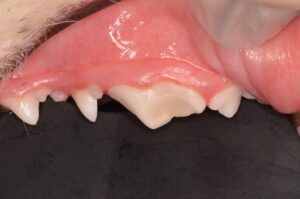

1歳のコーギーさん。鹿の角のおやつを与えていたところ、奥歯が欠けてしまったとのことで来院されました。

診察したところ、左上顎の大きな臼歯(第4前臼歯)が折れていて(破折)、さらには歯の中の神経・血管(歯髄)が露出している状態でした(露髄)。

この状態は、歯の中に口の細菌が侵入して感染を起こしてしまう状態です。放置すると歯の根の周囲にまで感染がすすんで膿が溜まり頬に穴が開くこともあります。